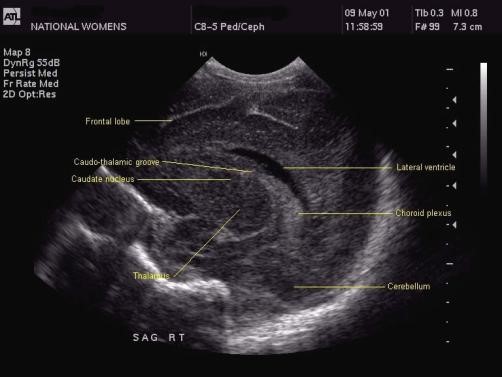

2. Angled Parasagittal

This neonatal head ultrasound shows the shape of the lateral ventricle. It is possible to see the caudate nucleus right below the frontal horn of the lateral ventricle with the thalamus right behind and below it. The occipital horn contains choroid plexus, whereas the choroid is in the caudothalamic groove, and it may or may not be echogenic.